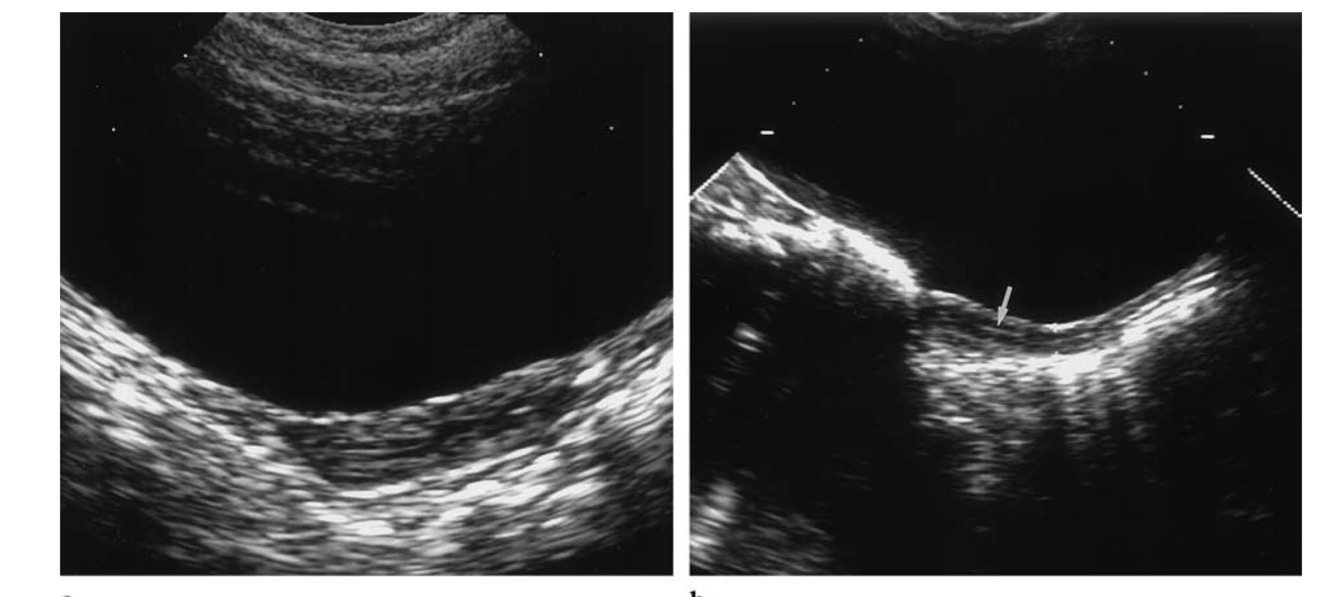

The prepubertal uterus has a tubular configuration (AP cervix equal to AP fundus) or sometimes a spade shape (AP cervix larger than AP fundus).

The endometrium is normally not apparent; however, high-frequency transducers can demonstrate the central lining.

The length is 2.5–4 cm; the thickness does not exceed 10 mm.

* Figure 2. Prepubertal uterus. (a) Longitudinal US scan obtained in a 5-year-old girl shows a tubular uterus; the anteroposterior diameter is 6 mm. (b) Longitudinal US scan obtained in a 6-year-old girl shows the endometrial lin- ing as a thin echogenic line (arrow).*